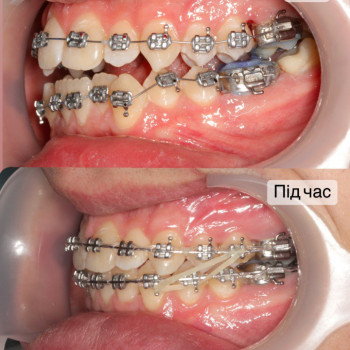

Якщо ти хочеш рівні зуби та красиву посмішку - тобі саме до нас!

Ми зробимо це на високому рівні!

А як саме наважитись на постановку брекетів?

Перший крок - це консультація ортодонта, Ви зможете дізнатись відповіді на запитання які Вас хвилюють. Перед постановкою брекетів усі зубки мають бути здорові, якщо ми бачимо карієс, його потрібно полікувати. Також потрібно зробити рентгенівські знимки для діагностики. За цей час, коли ми готуємо зуби до постановки брекетів, Ви зможете налаштуватись морально, звикнути з думкою що Ваша посмішка засяє новими барвами. На сьогоднішній час носіння брекетів являється престижним!